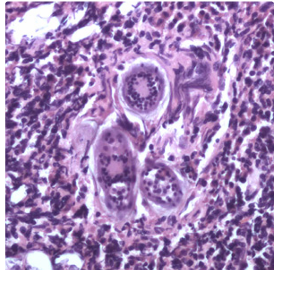

Figure E: __________in a urinary bladder biopsy specimen, stained with H&E. Images courtesy of the Michael E. DeBakey V. A. Medical Center, Houston, TX.

Eggs of S. haematobium